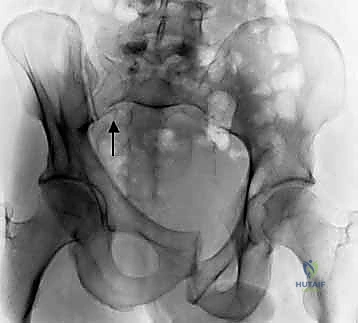

2. الأشعة السينية (X-rays): توفر نظرة أولية سريعة على كسور الحوض (AP, Inlet, and Outlet views).

3. التصوير المقطعي المحوسب (CT Scan): وهو المعيار الذهبي (Gold Standard) لتشخيص كسور الحوض والعجز. يقوم الدكتور هطيف باستخدام تقنية إعادة البناء ثلاثي الأبعاد (3D Reconstruction) لفهم هندسة الكسر بدقة متناهية قبل الدخول إلى غرفة العمليات.